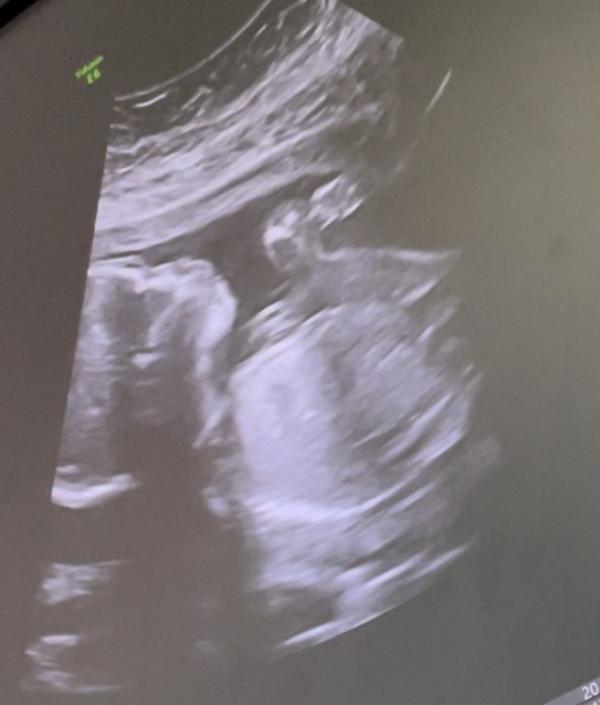

Беременность протекала легко (за исключением токсикоза до 14 недели), анализы все в норме, УЗИ и КТГ хорошие. Чувствовала себя хорошо, вела очень активный образ жизни. Наступил ПДР, признаков на начало родов ноль, чем была сильно огорчена. В ЖК получила направление на госпитализацию в 40,5 недель. 40,6 первая таблетка, ничего, 41 вторая, началось. Пришлось пить таблетки для стимуляции родовой деятельности, так как плод крупный 4000 грамм +/-500 грамм. Схватки начались со второй таблетки. Созвонилась с врачом с котором, договаривались о родах. Осмотрев меня на кресле в 9 утра, сказала, что раскрытие 2-3 см, ждём полного. Меня переводят в родовое отделение, одевают аппарат КТГ и уходят. Схватки усиливаются, промежуток между схватками 2 минуты и 30 секунд (да такое бывает если у вас стремительные роды)…тут мне муж пишет, скрин переписки приложу. Признаюсь, во время схваток были мысли: « полный наркоз и кесарево», но решила терпеть до последнего. Приходит анастезиолог и у меня появляется надежда на облегчение этих прям болезненных схваток, но не тут то было. Пока он пытался и делал анестезию столько оскорблений и грязи в свой адрес я не слышала никогда. К примеру: « стонать будешь дома, тут нечего; у меня тут валом таких как ты; наверное сотню весишь, куда вы такие рожать та лезете и т.д.». Я оболдела от его хамства, первая ЭА не подействовала, я медсестру попросила его позвать, он вернулся через час где-то, сделал вторую ЭА и тут я ему сказала, что вы такой злой, почему так себя ужасно ведёте? Он промолчал, но отношение немного изменилось в лучшую сторону ( честно, хотелось встать и разбить его рожу всем что под руки попадётся, ели сдержалась, нельзя вставать после укола ЭА). Вторая тоже не дала эффекта, пришла заведующая, говорит «вы рожаете, поэтому ЭА не действуют». Мой врач не поверила, что все так быстро происходит, посмотрев меня на кушетке, переводят на кресло. Во время схваток сквозь зубы сдерживала крик от боли, в отдых записывала голосовые мужу, как это мучительно и хорошо, что у нас не парные роды. 🤣 На кресле меня осмотрели и я началась тужится, первая потуга- поняла как это делать в реальности, на вторую моя трубочка изо рта полетела в акушерку, дула что есть мощи 😅, головка уже виднелась и мне врач предложил ее потрогать 😰я сказала «не надо, дайте я рожу» (изначально себя настроила никаких криков, слушать врача, без паники). На третьи потуги родилась наша Стефания 💕 3920 грамм, 56 см, в 13:00 этого же дня… Её крик-мои слёзы ❤️я счастлива!!! Развитие плода во время беременности как по часам, никто и подумать не мог, что роды будут стремительные, за 4-5 часов родила, Слава Богу! ☺️